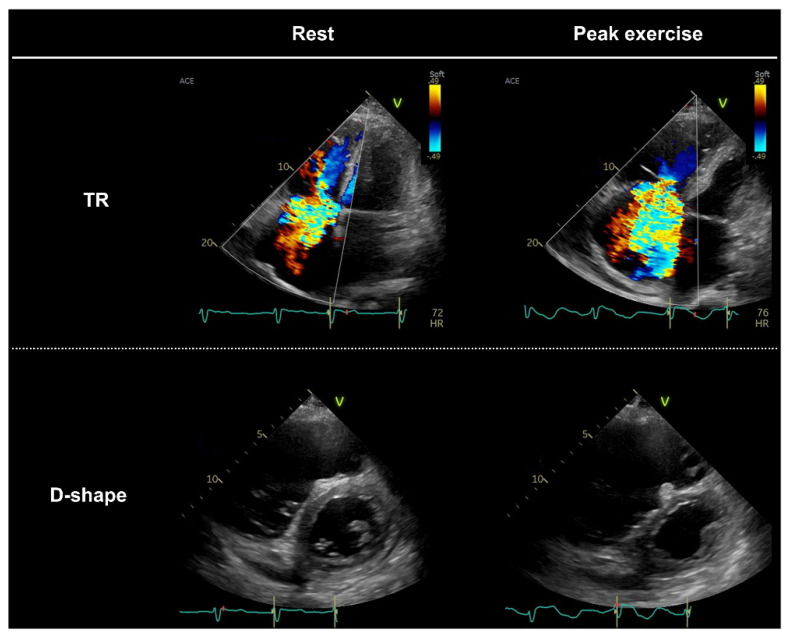

臨床心エコー図学 メジカルビュー社|循環器内科|循環器診療 ザ・ベーシック 心の詳細情報

メジカルビュー社|循環器内科|循環器診療 ザ・ベーシック 心。病態・類似疾患別心エコー図検査のルーティン[Web動画付。心臓超音波検査(心エコー / Echocardiography / UCG) - 神戸き。「臨床心エコー図学」吉川 純一定価: ¥ 35000ご覧いただきありがとうございます。たらこ様 臨床工学技士国家試験問題解説集 8回分。歯科CBT対策 CBT PASS 問題集1 基礎系・連問 第7版。書き込みなどはありません。